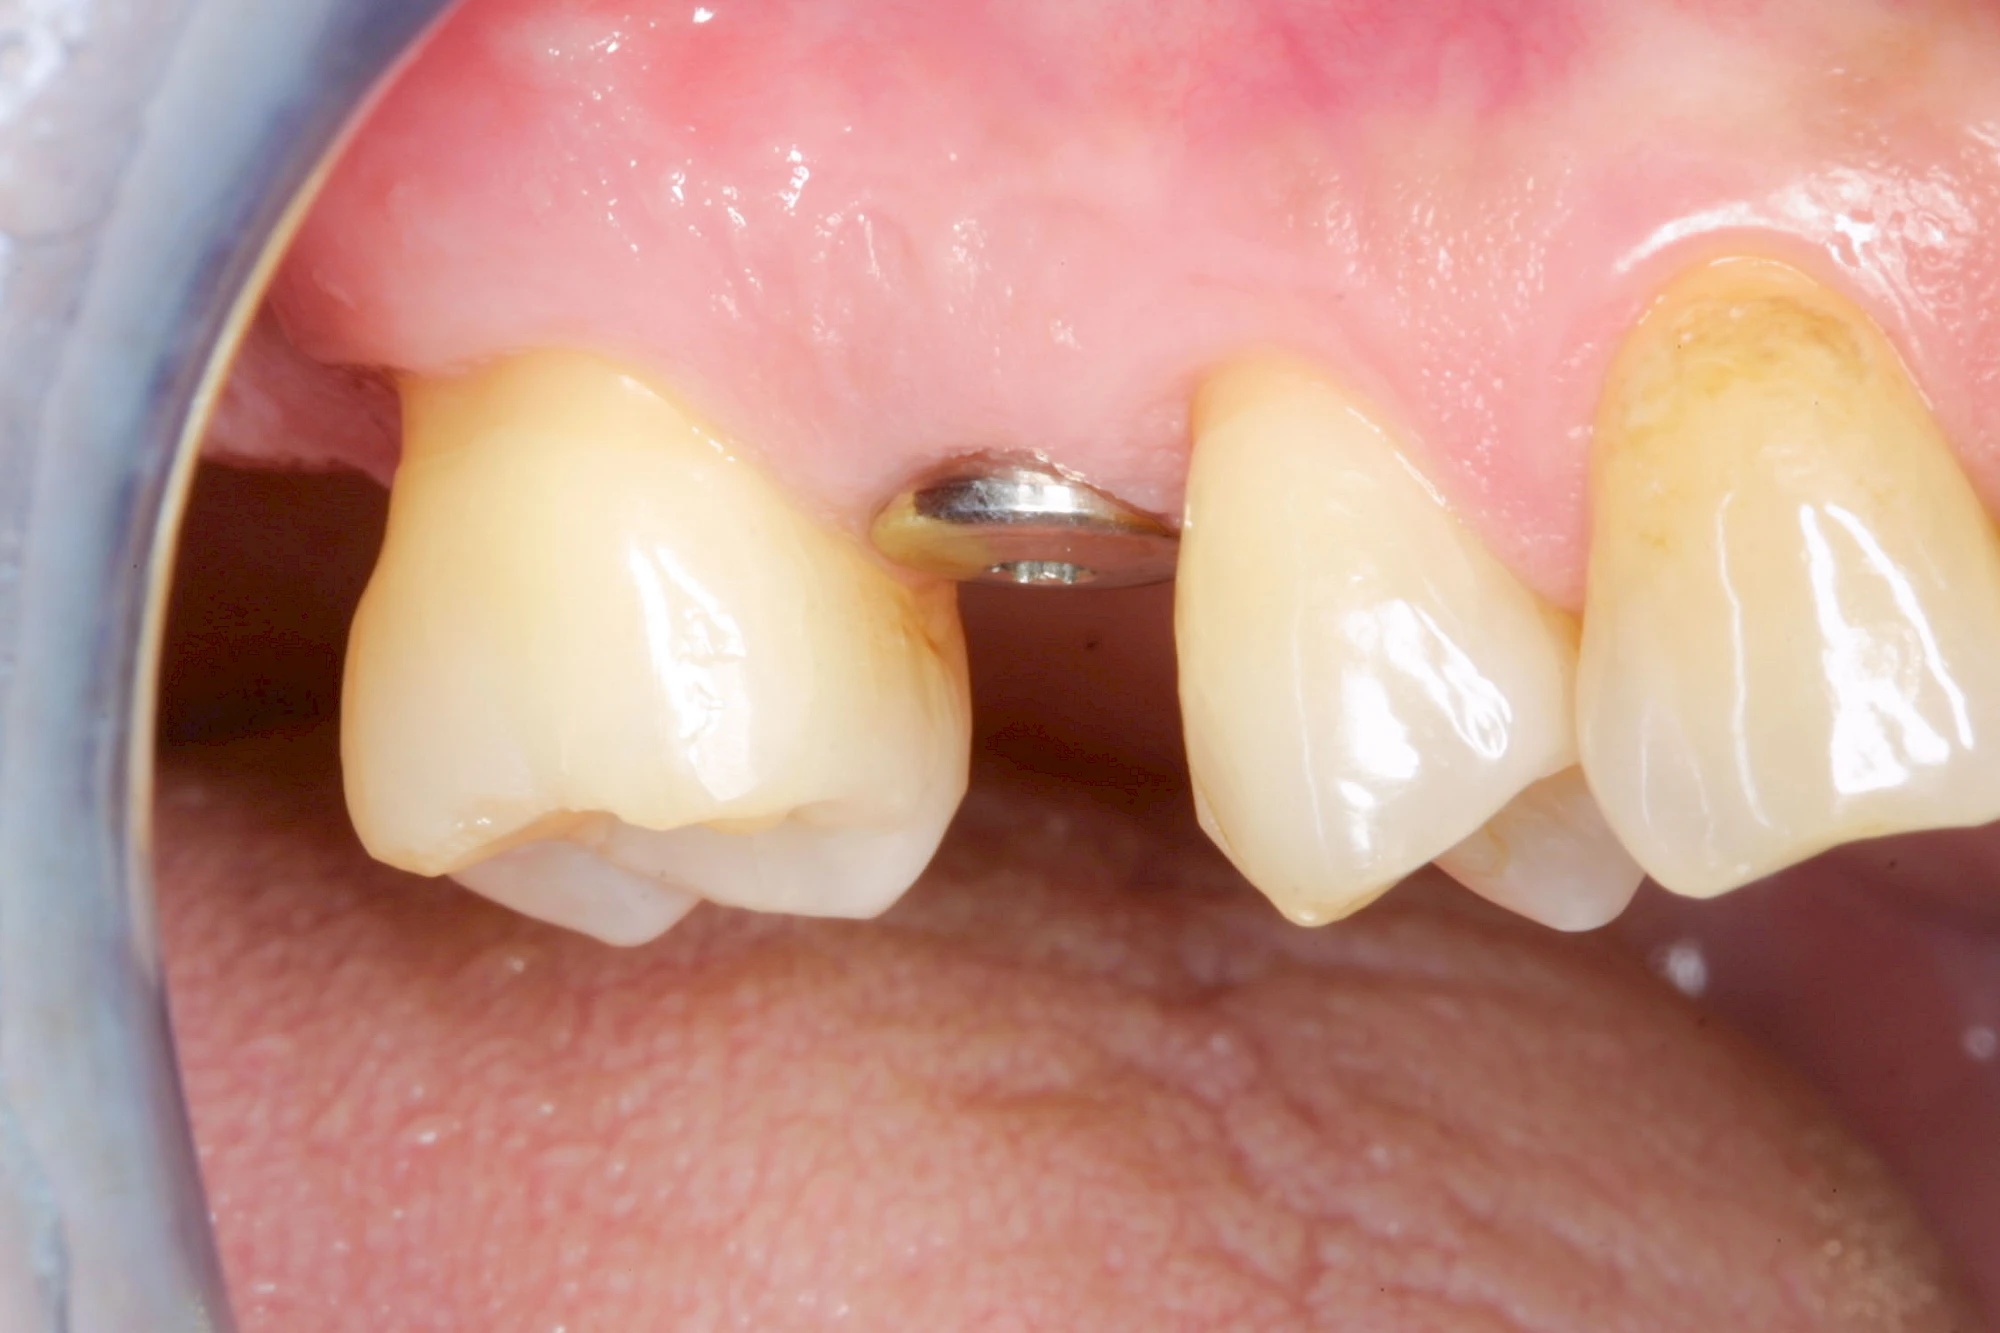

Implantate sind künstliche Zahnwurzeln. Nach einer gewissen Einheilzeit im Knochen (meist 3-6 Monate) erfolgt über einen separaten Aufbau (Abutment) die Befestigung einer Krone bzw. Brücke oder Zahnprothese.

Implantate: Kronen & Brücken

Fehlen einzelne Zähne und die Nachbarzähne sind unbeschadet oder gut zahnärztlich versorgt, werden immer häufiger Implantate gewählt, um die Lücken zu schließen. Auch bei größeren oder verteilten Lücken, wenn keine herausnehmbare Prothese gewünscht ist, werden Implantate für Kronen- bzw. Brückenversorgungen gesetzt. In Einzelfällen entscheiden sich sogar zahnlose Patienten für eine festsitzende Versorgung auf Implantaten.

Varianten zur Verankerung von festsitzendem Zahnersatz auf Implantaten